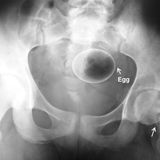

Diese Dinge gehören dort eigentlich nicht hin: Immer wieder passieren Unfälle, wenn Menschen sich zur sexuellen Stimulation über den After Gegenstände in den Darm einführen. Ob Orangen, Spraydosen oder Kaffeebüchsen - der Fantasie sind dabei offenbar keine Grenzen gesetzt.

Die Webseite radiopaedia.org zeigt, welche Dinge Ärzte auf Röntgenbildern schon entdeckt haben. Die Aufnahmen wirken skurril und erschreckend zugleich und machen deutlich, wie weit die eingeführten Dinge bereits in den mescnhlichen Darm vordringen können.

Aber Glück im Unglück für die Patienten: Die Gegenstände können meist ohne Operation entfernt werden. Sehen Sie hier einige der spektakulärsten Röntgenaufnahmen. Da runzeln selbst Chirurgen die Stirn.